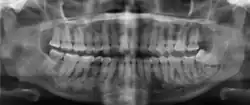

| Florid osseous dysplasia of the mandible | |

Cemento-osseous dysplasia (COD) is a benign condition of the jaws that may arise from the fibroblasts of the periodontal ligaments. It is most common in middle-aged females of African descent. The three types are periapical cemental dysplasia (common in those of African descent), focal cemento-osseous dysplasia (Caucasians), and florid cemento-osseous dysplasia (African descent). Periapical COD occurs most commonly in the mandibular anterior teeth while focal COD appears predominantly in the mandibular posterior teeth. Florid COD is an extensive variant of periapical COD where lesions occur in multiple quadrants which can encompass the maxilla and mandible, and infrequently can cause jawbone deformity.[1]

Diagnosis is based on clinical and radiographic observations, and in rare cases, biopsy may be performed.[3] Diagnosis is important so that the treating doctor does not confuse it for another periapical disease such as rarefying osteitis or condensing osteitis. Incorrect diagnosis could lead to unnecessary root canal treatments, or biopsy or surgical intervention which can be invasive and increase the risk of infection.[5] A pulp vitality test such as a cold test or electric pulp test can aid in diagnosis, since COD generally does not compromise pulp vitality.[6] COD can be found in individuals of all ages and ethnic backgrounds, but it has been observed more frequently in individuals of African, East Asian, and Asian descent.[7] Cone-beam computed tomography (CBCT) has proven useful in distinguishing between COD and periapical cysts, when examined with quantitative texture analysis using specialized software.[5]